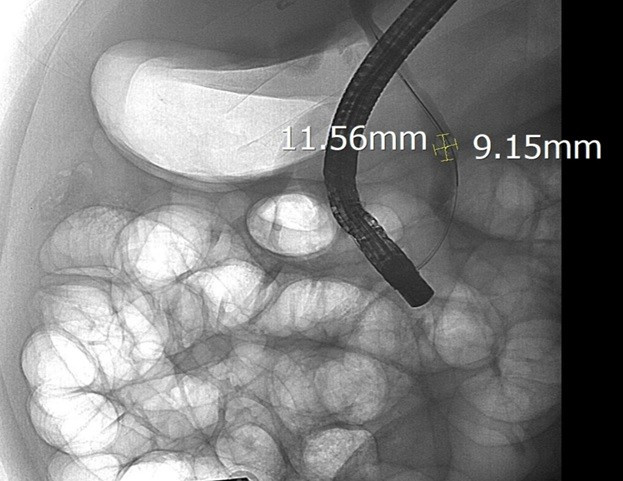

Sau khi hội chẩn, các bác sĩ Khoa Nội Tiêu hóa, Bệnh viện Hữu nghị đã chỉ định nội soi mật tụy ngược dòng (ERCP) dưới hướng dẫn của hệ thống chụp mạch số hóa xóa nền (DSA). Trong quá trình can thiệp, ê-kíp đã lấy thành công viên sỏi kích thước 11,5 x 9mm, giải phóng tình trạng tắc mật.

Hình ảnh sỏi ống mật chủ được lộ rõ dưới chụp DSA. Ảnh BVCC/Nguồn SKĐS